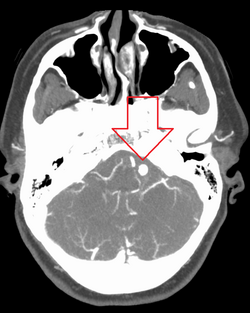

Ruptured 7mm left vertebral artery aneurysm resulting in a subarachnoid hemorrhage as seen on a CT scan with contrast

Diagnosis of a ruptured cerebral aneurysm is commonly made by finding signs of subarachnoid hemorrhage on a computed tomography (CT) scan. If the CT scan is negative but a ruptured aneurysm is still suspected based on clinical findings, a lumbar puncture can be performed to detect blood in the cerebrospinal fluid. Computed tomography angiography (CTA) is an alternative to traditional angiography and can be performed without the need for arterial catheterization. This test combines a regular CT scan with a contrast dye injected into a vein. Once the dye is injected into a vein, it travels to the cerebral arteries, and images are created using a CT scan. These images show exactly how blood flows into the brain arteries.[38]